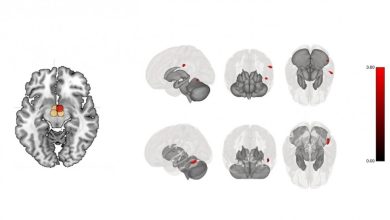

O exercício pós-cirurgia bariátrica modula regiões cerebrais associadas à regulação da ingestão alimentar

Conectividade hipotalâmica: vermelho indica aumento na conectividade cerebral após a intervenção, preto indica diminuição, bege indica nenhuma mudança. O painel…